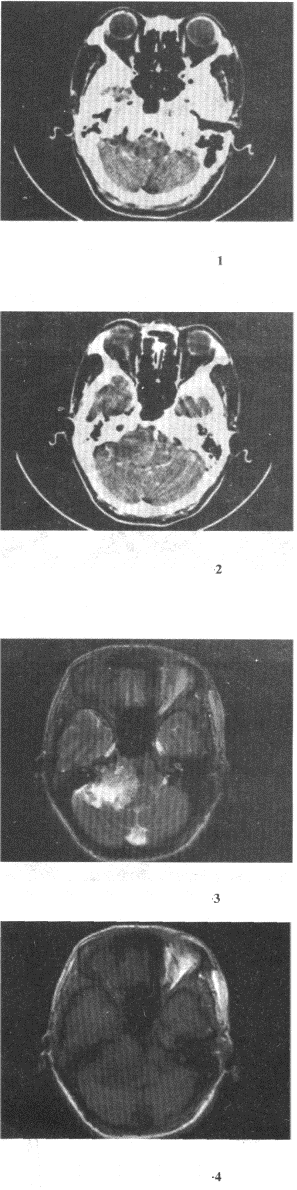

女,45岁,右耳听力下降半年余,CT检查如图,最可能的诊断是()